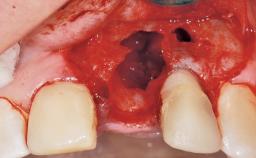

Late Placement of an Implant in a Maxillary Left Central Incisor Site

A 30-year-old female patient had lost tooth 21 and was referred to our clinic for consultation and treatment. Due to advanced apical infection, tooth 21 had been extracted two months earlier at another clinic and an acrylic-resin tooth had been bonded to the adjacent teeth. The patient desired implant treatment to avoid any damage to the adjacent natural teeth. While the patient had no history of any systemic disorder, she was a heavy smoker and exhibited medium to advanced periodontitis in the entire jaw. After the initial treatment to achieve a pocket probing depth of less than 4 mm and no bleeding on probing, a decrease in the height of the papillae mesial and distal to the extraction site and overall gingival recession were observed.

Bone Augmentation Horizontal|Staged

Augmentation Materials Autogenous chips|Membrane

Soft Tissue Grafting Simultaneous

Bone Volume Horizontally and vertically sufficient Horizontally deficient Deficient vertically or deficient vertically AND horizontally

Bone Volume Deficient horizontally, requiring prior grafting